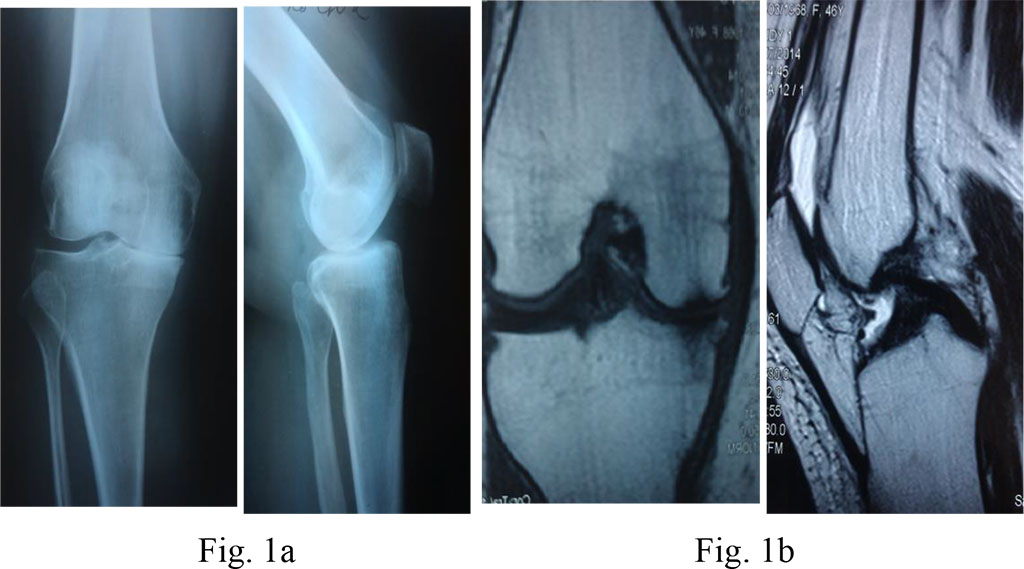

Diagnosis: III stage deforming arthritis of the left knee; varus deformity of the left knee; aseptic necrosis of the left femur’s medial process; pain syndrome.

Surgical treatment: a unicondylar arthroplasty of the left knee (Fig. 1a, b and 2)